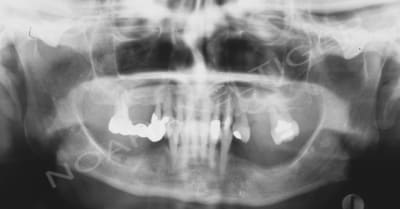

J'ai traité il ya de cela quelque temps un cas de réhabilitation globale sur terrain paro. Comme toi ikimine j'ai du faire face à un effondrement de DV, ce qui m'a amené à combiner paro, implanto, prothétique conventionnelle et occluso.

Voila les photos et radios initiales :

Opg initial pocr0a - Eugenol

Initial ou2oph - Eugenol

Radio initiales dq0rlp - Eugenol

Dents jugées comme devant extraites : 16, 14, 12, 24, 27

Dents jugées comme ayant un pronostic incertain : 22, 23

Facteurs importants à prendre en compte pour le plan de traitement : hauteur osseuse sous sinusienne réduite, crête très fine à la mandibule.

Souhait de la patiente : rehabilitation fixe au maxillaire. A la mandibule, la patiente est déja porteuse d'une PPAC qu'elle accepte parfaitement. La patiente souhaite seulement une meilleure rétention mais ne veut pas se lancer dans des travaux d'augmentation osseuse importants.